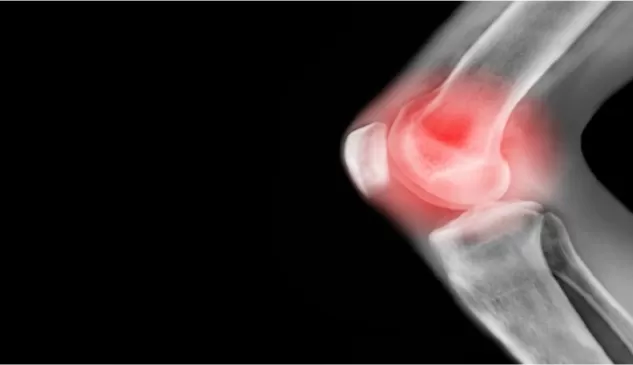

تخلص من الام المفاصل نهائياً مع هذا المشروب السحري الرهيب

على الرغم من عدم وجود علاج شاف لالتهاب المفاصل، إلا أن بعض الأطعمة يمكن أن تساعد في تقليل الأعراض

وفي حالة هشاشة العظام، يمكن لتغييرات نمط الحياة – بما في ذلك الخيارات الغذائية

-أن تقلل الألم وتساعد الناس على إدارة حالتهم بشكل أفضل، بينما يعيشون الحياة على أكمل وجهويمكن أن يساعد تناول الأطعمة المعروفة بخصائصها المضادة للالتهابات، أو الأطعمة التي تحتوي على مضادات الأكسدة، في تقليل الالتهاب.

ويحدث الفُصال العظمي عادة عند الأشخاص الذين تزيد أعمارهم عن 40 عاما، وهو أكثر شيوعا عند النساء.

ويؤثر الفصال العظمي على الغضروف – النسيج المرن الذي يبطن المفاصل – ما يجعل مفاصلك متيبسة ومؤلوفي الحالات الشديدة، حيث يصبح الغضروف متهالكا بشكل كبير، يمكن أن يعني ذلك احتكاك العظام بالعظام ويمكن أن يشوه شكل المفصل ويدفع العظام من موضعها.

ويؤثر الفصال العظمي بشكل شائع على:

• اليدين.

• العمود الفقري.

• الركبتين.

• الخوصرتين…